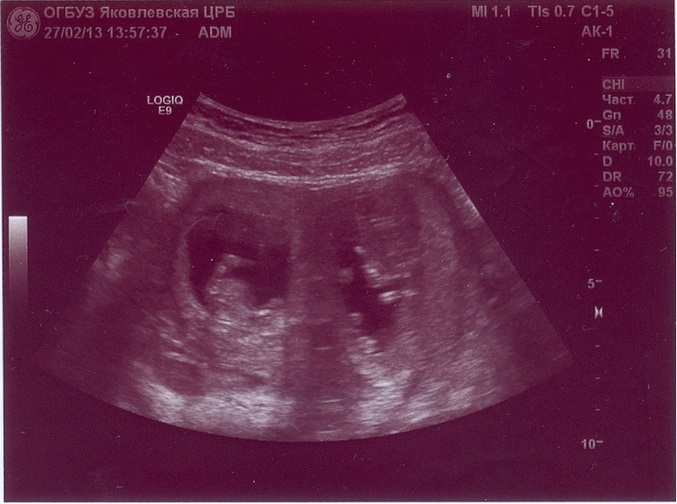

я внизу кинула фото.Посмотрите какие они

вот такие мы

здесь по-моему выглядит, как монохориальная